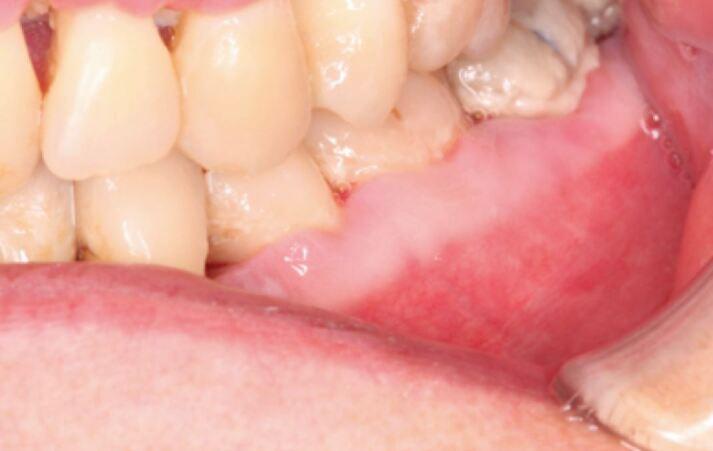

'Necrotising periodontal diseases' is an umbrella term for necrotising gingivitis, necrotising periodontitis, necrotising stomatitis and noma. These rapidly destructive conditions are characterised by pain, interdental ulceration and gingival necrosis which, if left untreated, can result in osteonecrosis. Research indicates that patients with a history of alcohol misuse are at an increased risk of malnutrition, which negatively affects the immune response and predisposition to necrotising periodontal diseases. This article will discuss that osteonecrosis of the alveolar bone does not exclusively occur in association with antiresorptive medications, but can occur as a severe form of necrotising gingivitis. In this article, we will describe two cases to highlight the occurrence, presentation and management of necrotising periodontal diseases secondary to alcohol misuse.

'坏死性牙周病'是坏死性龈炎、坏死性牙周炎、坏死性口炎和口底蜂窝织炎的统称。这些迅速破坏性的疾病的特征是疼痛、牙间溃疡和牙龈坏死,如果不治疗,可能导致骨坏死。研究表明,有酒精滥用史的患者更容易出现营养不良,这会对免疫反应和发生坏死性牙周病的倾向产生负面影响。本文将讨论牙槽骨骨坏死不仅与抗吸收药物有关,还可能作为严重的坏死性龈炎发生。在本文中,我们将描述两例病例,以强调酒精滥用引起的坏死性牙周病的发生、表现和治疗。